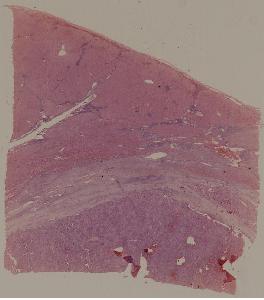

49.梅毒性主动脉炎

50.大叶性肺炎

51.肺肉质变

52.小叶性肺炎

57.肺癌

59.慢性萎缩性胃炎

60.胃溃疡

61.胃腺癌(胃粘液腺癌)

62.急性普通型病毒性肝炎

63.慢性活动性肝炎

64.急性重型病毒性肝炎

65.亚急性重型病毒性肝炎

66.活动性结节性肝硬化

67.非活动性结节性肝硬化

68.胆汁性肝硬化

69.肝细胞性肝癌

72.膜性肾小球肾炎

73.急性肾小球肾炎

74.新月体性肾炎

75.慢性硬化性肾小球肾炎